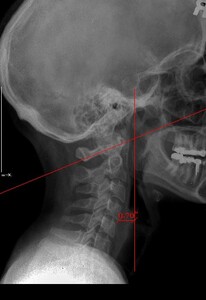

Upper cervical orthogonal based x-rays to measure for significant upper cervical misalignment.17,21,22 (Figure 2 a,b,c)

These films are used to determine atlas misalignment, develop a correction strategy and confirm an appropriate correction has been made.

The x ray measurements have been charted to show changes in Atlas laterality, Atlas rotation and degrees of change in angular rotation (measurement in degrees that the cervical spine is off the vertical axis). (Table 3).